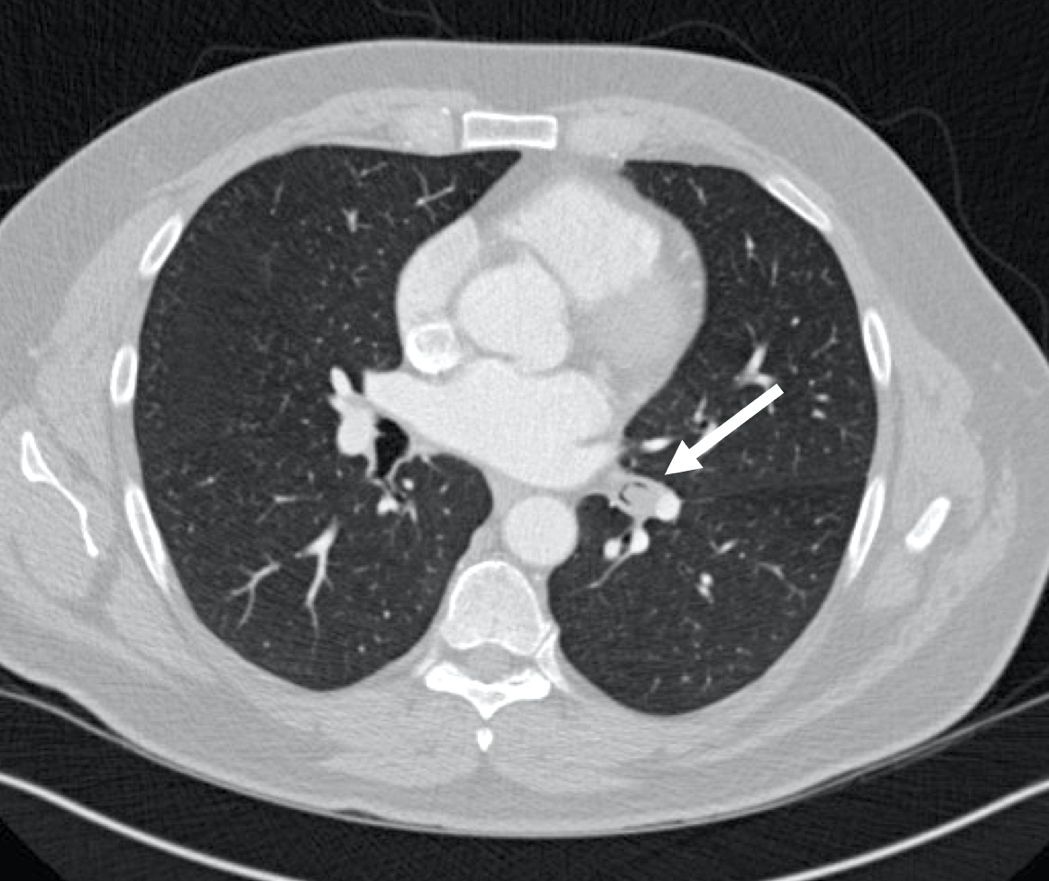

Radiology description

- Chest CT scan

- Lobulated and well circumscribed nodule implicating major bronchi

- Obstruction signs (atelectasis, bronchiectasis) can be seen (AJR Am J Roentgenol 2011;197:1073)

- Positron emission tomography (PET) scan: low to moderate uptake (mean standardized uptake value [SUV]: 3.4)

Radiology images